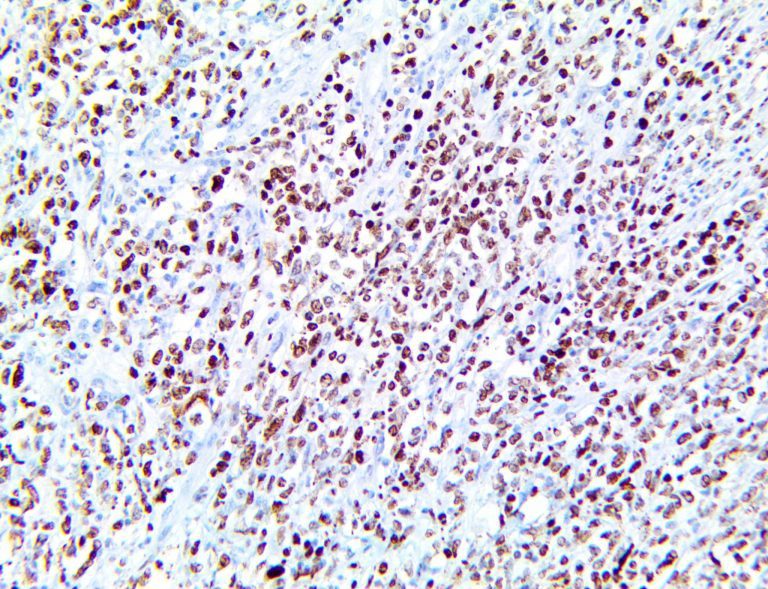

It is the ICU physician who is most likely to witness one of the deadliest manifestations of the abnormal immunological response, the cytokine storm syndrome (CSS). This response is also referred to by some as the cytokine release syndrome (CRS). CSS is characterized by continuous activation and expansion of macrophage and lymphocyte populations, which secrete large amounts of cytokines, causing the cytokine storm. This massive cytokine release is akin to hemophagocytic lymphohistiocytosis (HLH) disease, a syndrome characterized by initial unchecked and persistent activation of cytotoxic T lymphocytes and NK cells.

Clinical and laboratory manifestations of HLH include fever, enlarged liver and/or spleen, neurologic dysfunction, coagulopathy, liver dysfunction, cytopenias (i.e., low levels of erythrocytes, leukocytes, and/or platelets), hypertriglyceridemia, hyperferritinemia, hemophagocytosis, and eventually diminished NK cell activity as the immune system becomes progressively paralyzed. HLH can be familial (primary HLH) or secondary to another disease process (sHLH), such as rheumatic disease, in which it is referred to as macrophage activation syndrome (MAS, characterized by elevated ferritin).